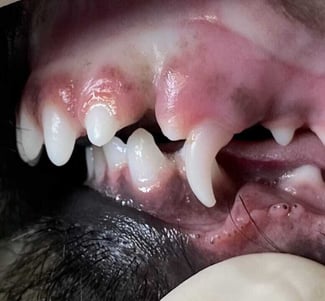

Interceptive orthodontics is the term used to describe the extraction of a deciduous or permanent tooth that obstructs comfortable occlusion in order to establish a comfortable, atraumatic occlusion. We usually extract a less significant tooth to save a strategically more important one. This remains an effective approach to address the consequences of malocclusion even though the remaining tooth might be the one in an anatomically abnormal position ( Figure 2).

An example would be an abnormally positioned mandibular canine tooth that occludes on the palatal aspect of a maxillary incisor. If left untreated, this would cause attrition to both of the teeth involved. Pressure exerted by the abnormal position of the canine would cause displacement of the maxillary incisor labially and prevent normal eruption of the associated mandibular canine tooth. The abnormal positioning of the mandibular canine could also cause impingement of the mandibular canine on the palate.

The sacrifice of a maxillary incisor tooth would then allow unobstructed eruption or occlusion of an abnormally positioned mandibular canine tooth. This would be less invasive and accommodate retention of the strategically more important mandibular canine tooth ( Figure 3).